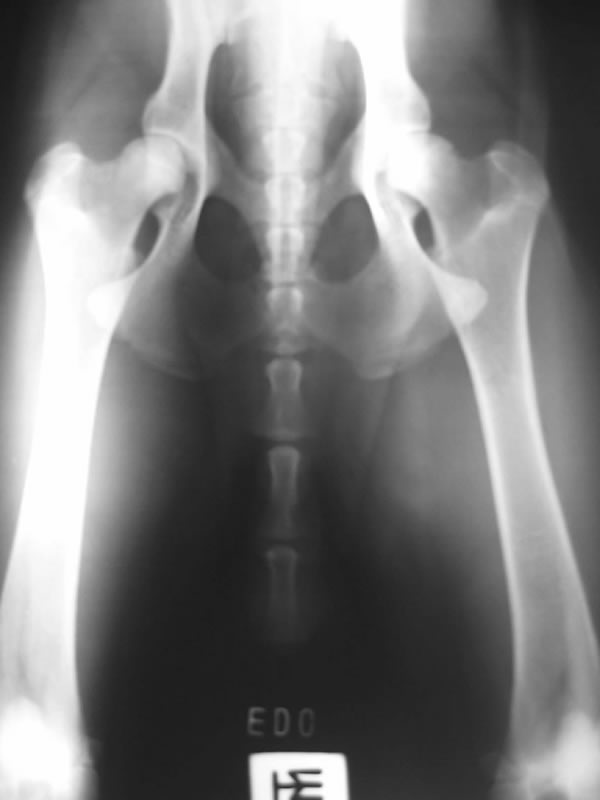

Eddy is a beautiful son of Anouc-Lar Leomegy (Nuky) and Agala Zomboch daughter of top producing stud 6XWUSV 5XFCI Emir Chabet, born December 25, 2003. He is line bred to 2XBSP Troll vom Körbelbach. He is a huge male with a very good temperament. He is good with kids and very tolerant with other animals. He likes bite work, tracking and watching Animal Planet. His obedience on field an off field is coming along very nicely. We took Eddy for his OVC certification and the veterinarian said Eddy has the best hips she's seen in five years on a GSD.

Eddy's X-Rays